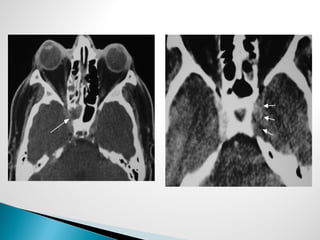

 Radiographic studies

◦ CT sinus

◦ MRI to assess tissue invasion, and orbital, intracranial, or

neural involvement

◦ Findings

 CT

 Bone erosion and extrasinus extension – classic finding

 Severe, unilateral mucosal thickening

 Thickening of periantral fat planes

 MRI

Obliteration of the periantral fat

Leptomeningeal enhancement (intracranial extension)

Granuloma formation

○ Hypointense on T1 and T2

Extrasinus extension

Cavernous sinus involvement

○ Absent flow void of carotid

○ Soft tissue thickening of the involved sinus

Axial MRI, T2 – left sphenoid sinus

with central hypointense region with

surrounding hyperintensity. Flow

void in left cavernous sinus absent

(arrow)

Axial MRI, T2 – Acute infarction of the

left temporal lobe in same patient